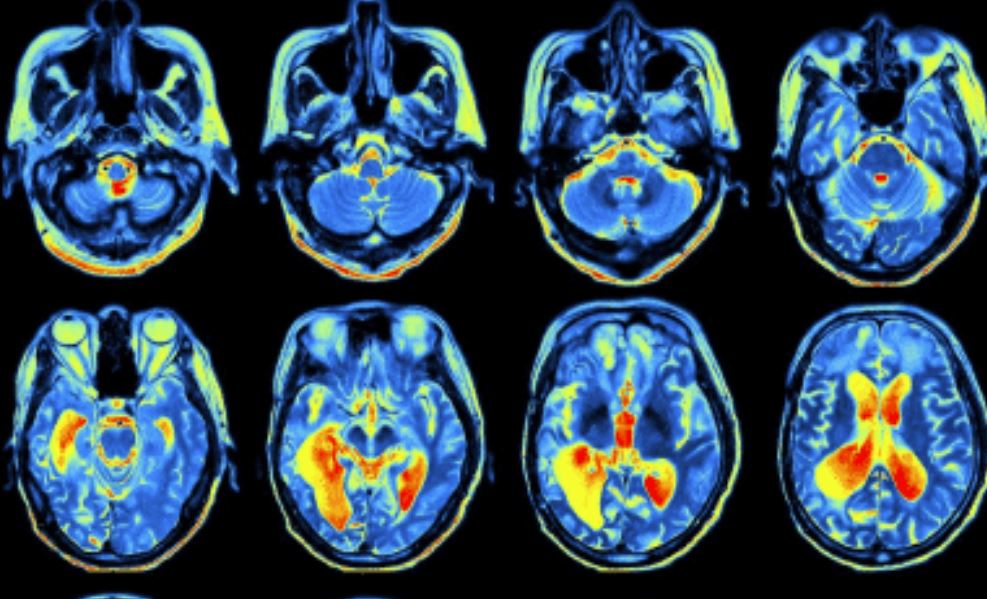

Proving a Traumatic Brain Injury

Dr. David Levy “Proving a TBI” PDF File

Use of DTI to Prove TBI

mTBI Tutorial